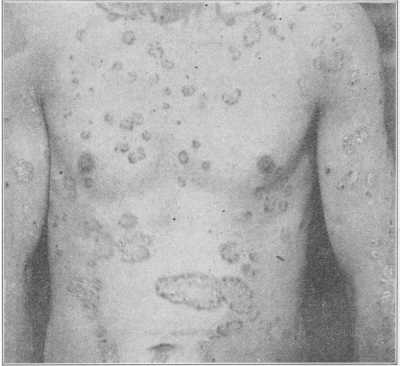

Fig. 11.

Erythema Multiforme, in which many of the lesions have become bullous—

Erythema Bullosum.